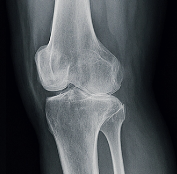

무릎 연골 손상 증상 진단 방법

정확한 진단은 치료 방향 설정의 핵심입니다.

- 문진과 이학적 검사: 통증 위치, 무릎의 가동 범위 확인

- X-ray: 연골은 직접 보이지 않지만 간접적 관절 간격 확인 가능

- MRI(자기공명영상): 연골 손상 위치와 정도를 정밀하게 파악

- 관절 내시경 검사: 직접 무릎 내부 확인 및 치료 가능

특히 MRI는 무릎 연골 손상 증상 진단에 가장 효과적인 검사입니다.